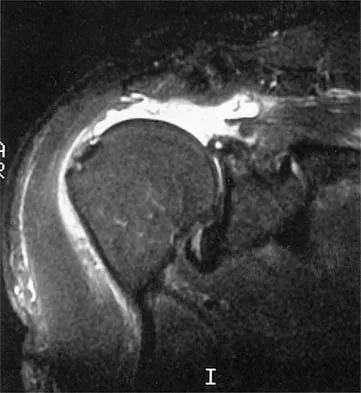

A 47-year-old man has acute right shoulder pain after falling off a ladder. The MRI scan shown in Figure 9 reveals

Correct Answer: a full-thickness rotator cuff tear.

The MRI scan reveals a full-thickness rotator cuff tear with retraction and increased signal in the subacromial space indicating joint fluid. Herzog RJ: Magnetic resonance imaging of the shoulder. Instr Course Lect 1998;47:3-20.

Iannotti JP, Zlatkin MB, Esterhai JL, et al: Magnetic resonance imaging of the shoulder: Sensitivity, specificity, and predictive value. J Bone Joint Surg Am 1991;73:17-29.